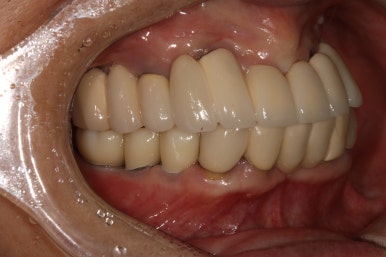

어금니 좌측

좌우측 측면 사진 비교시, 아래 어금니 임플란트로 깔끔하게 메꿔진 빈 공간이 인상적입니다!